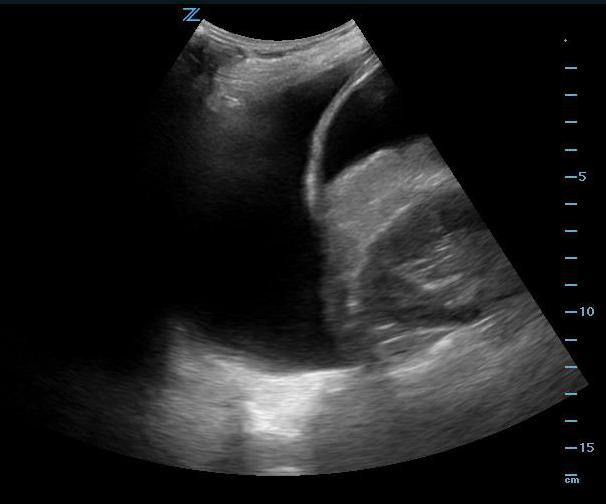

- Pelvic Views

- Pelvic views are not as easy to obtain as right upper quadrant views, but since the pelvis is the most dependent part of the peritoneal space, it is the most likely place to see abdominal free fluid.

- Place the probe in the midline just cephalad to the pubic bone with the transducer indicator pointed cephalad. Make sure the probe position is correct by actually placing the probe on the pubic bone and noting a bone shadow on the image. (Fig. 14) From this position sliding the probe slightly cephalad will produce a longitudinal pelvic view.

- The bladder will be found just cephalad to the pubic bone and can usually be found even if it is nearly empty. A full bladder will be triangular in shape. The lower angle of the bladder marks the border between the intraperitoneal space (left side of the image) and the true pelvic structures (right side of the image).

- In a male, free fluid will be seen along the inferior peritoneal cavity just posterior to the wall of the bladder.

- In a female, the body of the uterus sits in the intraperitoneal space just posterior to the bladder (Video 19), so free fluid will be seen just posterior to the uterus, also known as the pouch of Douglas. A trace amount of free fluid can be normal in the pouch of Douglas depending on the woman’s menstrual cycle. Free fluid often is seen here first. (Video 20) Free fluid may also be seen completely surrounding the edges of the uterus. (Video 21) If there is clot in the pelvis, this will look grey compared with unclotted blood which will be black. (Video 22)